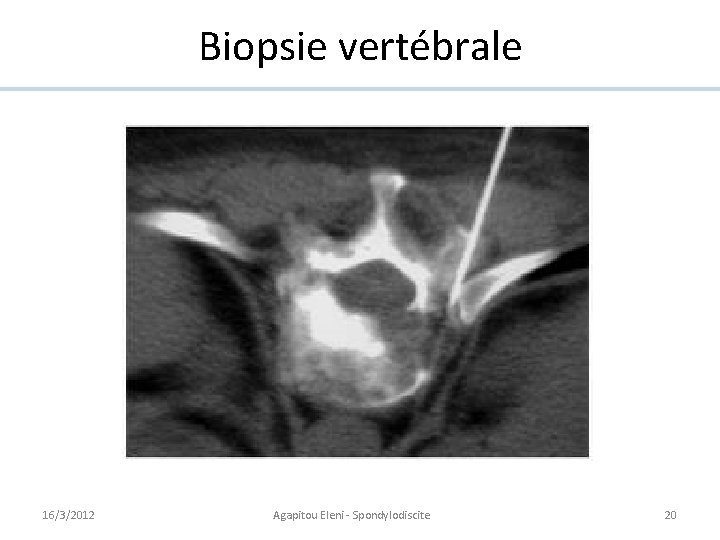

Biopsie • Nécessaire confirmation du diagnostic et identification du germe. • Pas de biopsie seulement si hémoc (+) pour germe typique. • Procédure ouverte ou par aspiration sous guidance par CT. • 2 prélèvements: ü Coloration de Gram et culture. ü Histopathologie: nécrose et résorption osseuse. 16/3/2012 Agapitou Eleni - Spondylodiscite 19

Biopsie vertébrale 16/3/2012 Agapitou Eleni - Spondylodiscite 20